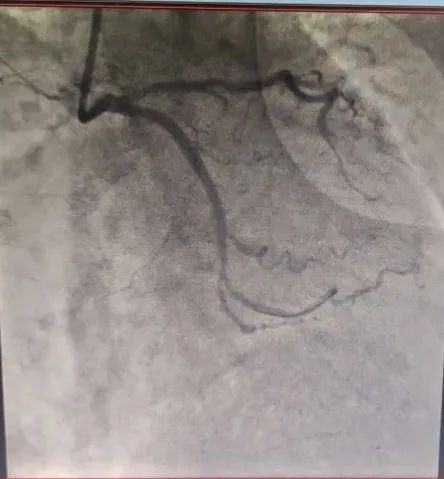

LCX血管狭窄明显改善

患者为78岁女性,主因间断胸闷3年就诊,冠状动脉CTA提示冠状动脉严重钙化,左主干管壁多发钙化,管腔狭窄,前降支严重钙化伴管腔狭窄大于70%,回旋支严重钙化伴有管腔严重狭窄。由于钙化严重,术前刘巍主任团队就做好了充分的准备。冠状动脉造影提示左前降支严重钙化伴有多发斑块管腔偏细,回旋支远段85%狭窄,右冠状动脉全程钙化伴有多发斑块。计划使用IVUS对回旋支狭窄进行评估,但IVUS无法通过近段病变,IVUS提示近段钙化角度大于270°。刘巍主任使用1.25mm磨头对回旋支进行旋磨,旋磨后,球囊及IVUS可顺利通过钙化病变到达远端,IVUS提示管腔弥漫性斑块,斑块负荷重,远段管腔严重狭窄,刘巍主任决定植入支架,经旋磨后,支架可顺利通过钙化病变部位,成功释放,支架膨胀效果良好。术后患者胸闷明显缓解。